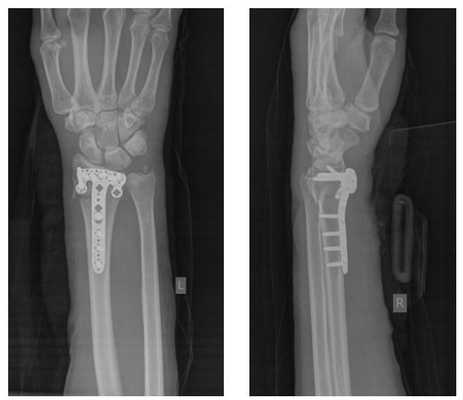

Лечение переломов лучевой кости

Перелом «луча в типичном месте» обычно возникает при прямом падении на вытянутую руку. Помимо резкой боли в руке, может появиться штыкообразная деформация, изменение положения кисти. В процесс перелома бывают вовлечены нервы и сосуды запястья, которые могут быть зажаты отломками, что проявляется онемением в пальцах, похолоданием кисти.

Для уточнения характера перелома и выбора дальнейшей тактики лечения используется рентгенография, в ряде случаев - компьютерная томография. Иногда требуется УЗИ кистевого (лучезапястного) сустава.

Поскольку лучевая кость примыкает к кисти, очень важно восстановить анатомию и объем движений в суставе, чтобы в дальнейшем избежать проблем с ним. Раньше такие переломы лечили только консервативно, в гипсовой повязке, но часто отломки смещались, кость срасталась неправильно, что в дальнейшем сказывалось на функции конечности - рука не сгибалась и/или не разгибалась до конца - формировалась тугоподвижность сустава (контрактура), оставался болевой синдром. К тому же длительное пребывание в гипсе отрицательно сказывалось на кожных покровах.

Оперативное лечение перелома лучевой кости (остеосинтез)

Практически все переломы лучевой кости со смещением требуют оперативного лечения - сопоставления и фиксирования отломков кости - остеосинтеза. Именно этот метод позволяет восстановить функцию кисти наиболее полноценно и добиться хороших функциональных результатов.

Лучевая кость первично срастается примерно за 6-8 недель, однако полная перестройка кости продолжается до 2 лет после перелома. Спустя этот срок пациент может начинать полноценно пользоваться рукой. Но разрабатывать руку с помощью определенных, рекомендованных врачом, упражнений, благодаря использованию фиксаторов можно уже в первые сутки после вмешательства. Легкие спортивные физические нагрузки можно начинать примерно спустя 3 месяца после операции.

В зависимости от типа перелома (оскольчатый, многооскольчатый, со значительным или незначительным смещением) можно выделить несколько возможных вариантов фиксации -пластиной, фиксированной винтами; аппаратом внешней фиксации; винтами или спицами.

Остеосинтез лучевой кости пластиной

При значительном смещении отломков используется остеосинтез лучевой кости металлической пластиной, специально разработанной для данной области. После сопоставления отломков, пластина фиксируется винтами к поврежденной кости. После установки пластины, на кожу накладываются швы, также применяется гипсовая лонгета. После операции назначается лекарственная терапия: обезболивающие препараты, препараты кальция для стимуляции сращения кости, при необходимости - препараты местного действия для уменьшения отека. Средний срок пребывания в стационаре - 7 дней. Швы снимаются в спустя 2 недели, на контрольном приеме у травматолога, тогда же пациент отказывается и от гипсовой повязки. Рука находится в возвышенном положении на косыночной повязке. Необходимости в удалении пластины, как правило, нет.